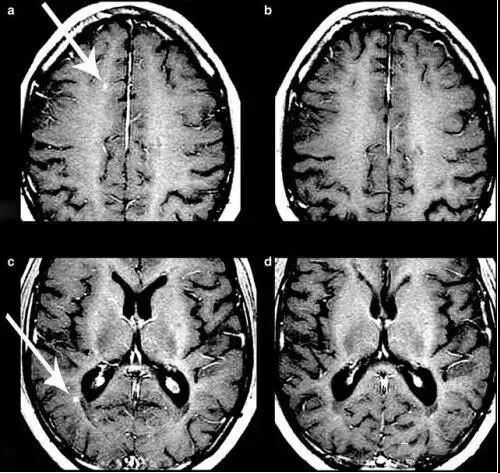

2012年,《柳叶刀·神经病学》上发表的一项研究显示,间充质干细胞治疗继发性、进行性、多发性硬化症是安全的,治疗后患者视力得到改善,视神经面积增加。